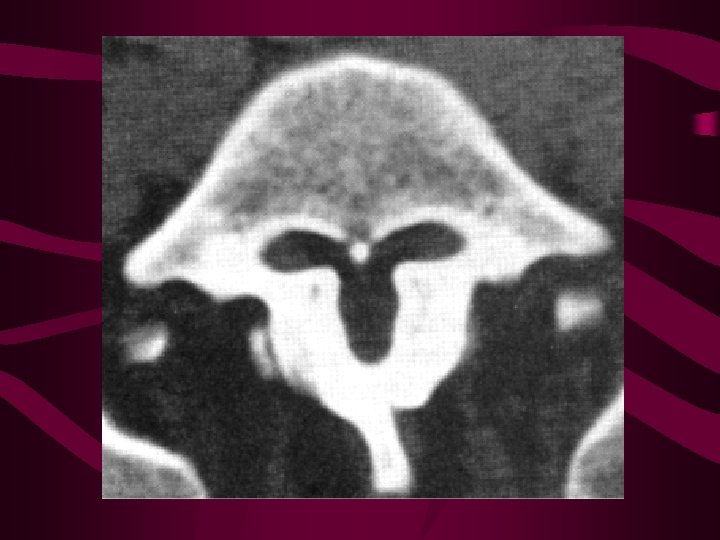

Cervical Disc Degeneration • • Uncinate processes form and extend upwards uncovertebral joint capsular forms disc splits to form articular surface disc splits progress medially and meet nucleus disappears posterior disc becomes bi-valved disc and vertebral height loss